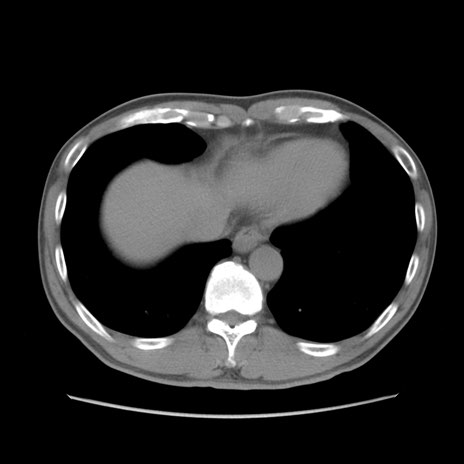

症例56 CT(横断像)

症例